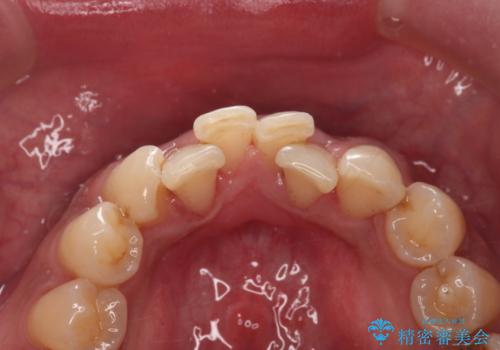

PMTC(60分コース) 担当衛生士 進藤

歯の着色だけでなく、汚れもとれ歯の表面がツルツルなって気持ちがいいと

大変満足していただけました。